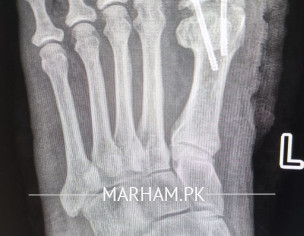

Talk to Orthopedic Surgeon on Post Operation X-ray

AoA, kindly ye meri mother ki xray report daikh kar bta dain k operation theek ho gya hai, X-ray main fracture nazar aa rha hai lekin, technician ny b kaha k fracture show ho rha hai kisi doctor ko dikha dain. shukria

Better to consult your treating surgeon again please.

Thank you

Need following informations

1- Date of injury or weeks

2- XRay before Surgery

3- XRay just after surgery

4- XRay latest , you already shared

Regards

get examined by surgeon for complete history and details regarding surgery.

Osteotomy means cutting the bone to straighten it, usually to relieve pain or improve joint function. After the cut, the bone is held in place with plates, screws or pins while it heals. Most people need a period of limited weight‑bearing followed by physical therapy to rebuild strength and range of motion. Recovery can take several months, and the goal is to return to normal activities, but some patients may still need braces or activity adjustments. The procedure is common for knee, hip or foot problems, and outcomes are generally good when the surgeon’s plan matches the patient’s anatomy and the rehab is followed closely. If you’re considering it, talk to an orthopedic surgeon about your specific condition, the expected healing time, and any lifestyle changes that will help you recover fully.